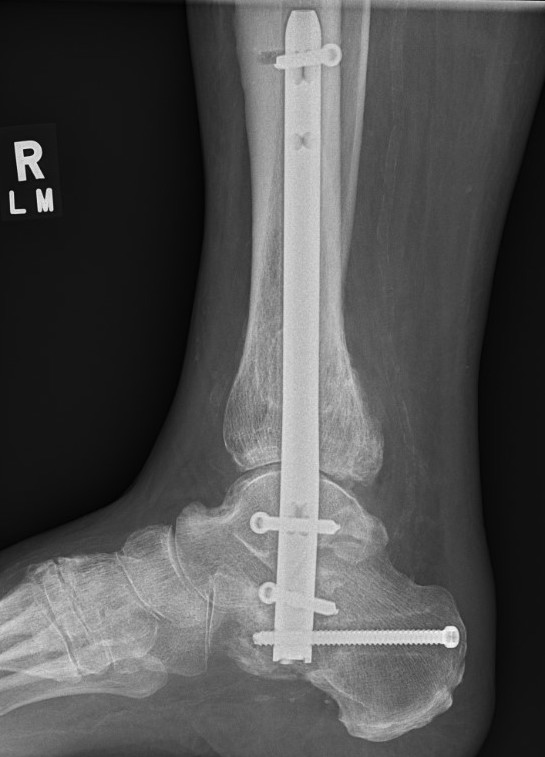

Tibiotalocalcaneal (TTC) / hindfoot nail

Insertion point

- in line with 2nd metatarsal / center of heel pad

- junction of posterior 2/3 and anterior 1/3 heel

- should pass through anterior aspect posterior subtalar joint

- posterior to lateral plantar artery and nerve

Screw fixation

- distal screw fixation in calcaneum +/- talus with jig

- compression

- proximal screws medial to lateral